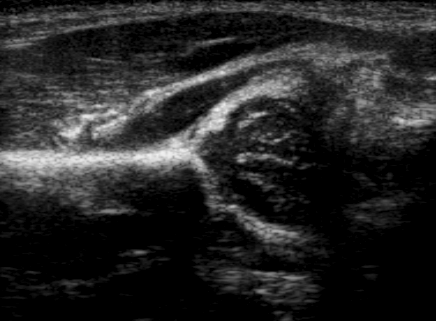

고관절 이형성증은 초음파[42]와 투사 방사선 촬영(X-ray)[43]으로 진단할 수 있다. 초음파 영상은 대퇴골두의 골화가 제한적인 4개월까지 선호되는데, 이는 출생 후 초기 몇 달 동안 고관절을 영상화하는 데 가장 정확한 방법이다. 하지만 생후 3~4주 전에는 생리적인 정상 이완성 때문에 초음파 검사를 해서는 안 된다.[46][47]

초음파[42]와 투사 방사선 촬영(X-ray)[43]이 진단에 사용될 수 있다. 초음파 영상은 대퇴골두의 골화가 제한적인 4개월까지 선호되며, 출생 후 초기 몇 달 동안 고관절을 영상화하는 데 가장 정확하다.[46] 그러나 대부분의 경우 생후 3~4주 전에는 초음파 검사를 수행해서는 안 된다.[46][47] 미국 소아과학회에서는 신생아의 보편적인 초음파 검사를 권장하지 않는다.[44]

고관절 이형성증은 초음파[42] 및 투사 방사선 촬영("X-ray")으로 진단할 수 있다.[43] 초음파 영상은 대개 4개월까지 선호되는데, 이는 그때까지 대퇴골두의 골화가 제한적이기 때문이며, 출생 후 처음 몇 달 동안 고관절을 영상화하는 데 가장 정확한 방법이다. 그러나 대부분의 경우, 생리적인 정상적인 이완성 때문에 생후 3~4주 전에는 초음파 검사를 수행해서는 안 된다.[46][47] 보편적인 초음파 검사와 표적 초음파 검사를 비교했을 때, 전자는 고관절 이형성증의 늦은 진단을 거의 줄이지 못하며, 이것이 미국 소아과학회에서 신생아의 보편적인 초음파 검사를 권장하지 않는 이유이다.[44]